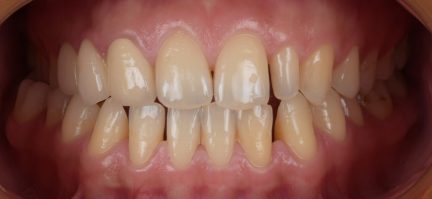

État final

Résultats obtenus

- Relation de Classe I obtenue

- Guidage fonctionnel des canines des deux côtés

- Surplomb et recouvrement normaux obtenus

- Ligne esthétique du sourire obtenue

- Cas où tous les objectifs de traitement ont été atteints

- Arcades harmonieuses obtenues

- Après traitement orthodontique, la partie supérieure droite 3, un implant posé et toutes les dents antérieures ayant reçu une restauration esthétique ont été utilisées.

- Le patient était très satisfait de l'effet curatif.